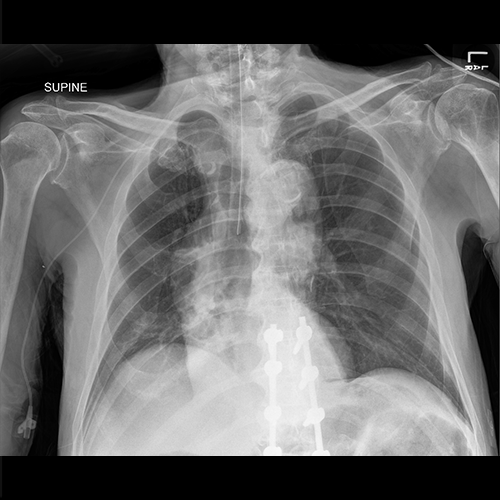

AP Chest X-ray

There is a non-specific fluffy infiltrate in the right lower lung field. The endotracheal tube is at the level of carina. The ETT should be 3cm above the carina and therefore should be retracted by 3cm.

A chest x-ray is the best first imaging study as it can be obtained quickly, can indicate the presence of pneumonia, and can rule out other life-threatening pathologies. The chest x-ray will also confirm appropriate endotracheal tube and PICC placement. The X-ray can also detect a pneumothorax, a known PICC line placement complication.